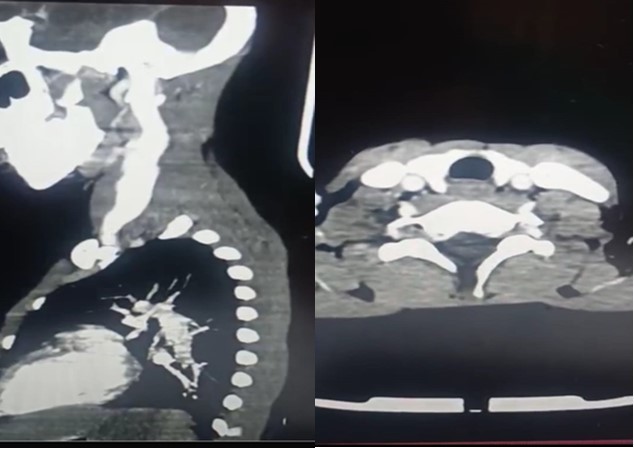

Ultrasonography (USG) of the neck showed fusiform dilatation of the lower segment of the IJV with a caliber of 4cm increasing to 7cm on Valsalva maneuver. In a previous USG imaging 3 years ago, it was about 2cm and 4 cm consecutively. Contrast-enhanced computed tomography (CT) of his neck and mediastinum excluded any mediastinal mass or anomaly and confirmed the previously known dilatation of the left internal jugular vein without thrombosis (Figure 2).

Figure 2.(c Left,d Right) (c) sagittal CT-image shows well-defined (d) axial CT-image showing dilated left IJV with homogenous huge left IJV